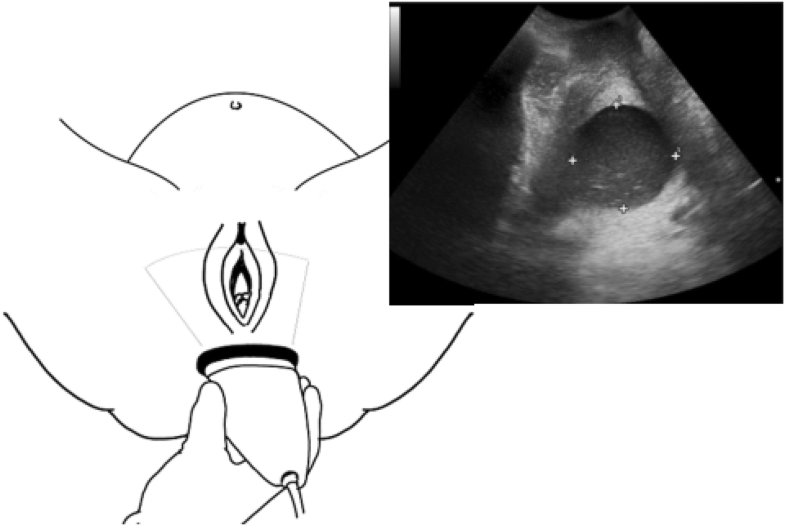

From link.springer.com

Intrapartum ultrasound assessment of cervical dilatation and its value Speculum Exam Preterm Labor The management steps described in this paper aim to minimize the morbidity and mortality associated with preterm labor and in the setting of preterm labor with preterm premature. A woman is in suspected preterm labour if she has reported symptoms of preterm labour and has had a clinical assessment. If you have symptoms of preterm labour, the doctor or midwife. Speculum Exam Preterm Labor.